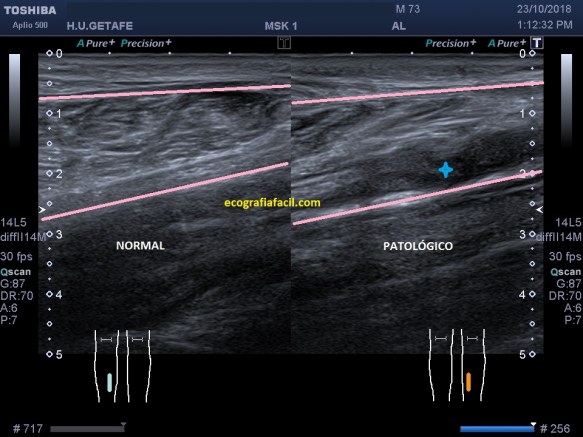

Compara la imagen 1 y la 2, grábala en tu memoria fotográfica. Ambas son unas imágenes en corte longitudinal del teste derecho de dos pacientes distintos.

La imagen 3 y 4 son parte estudian en eje largo y corto las medidas de la lesión en los tres ejes del espacio, en ocasiones, podemos tener más de una lesión. Siempre super atentos si las lesiones son intra o extratesticulares.